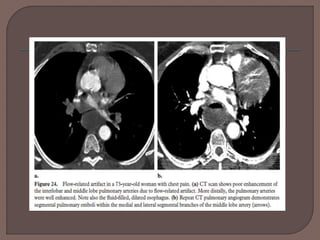

 Bilateral lower lobe flow-related artifacts due to poor

mixture of blood and contrast material can cause

transient interruption of contrast enhancement.

 Transient interruption of contrast enhancement is likely

related to inspiration and to unenhanced blood

entering the right atrium, right ventricle, and pulmonary

arteries from the inferior vena cava just prior to image

acquisition.

 A flow-related artifact can be confidently diagnosed by

identifying its ill-defined margins and by demonstrating

an attenuation level above 78 HU.

 As CT scanners become faster, delaying initial image

acquisition until approximately 5 seconds after

inspiration should allow the transient interruption in

contrast material to pass through the pulmonary

circulation